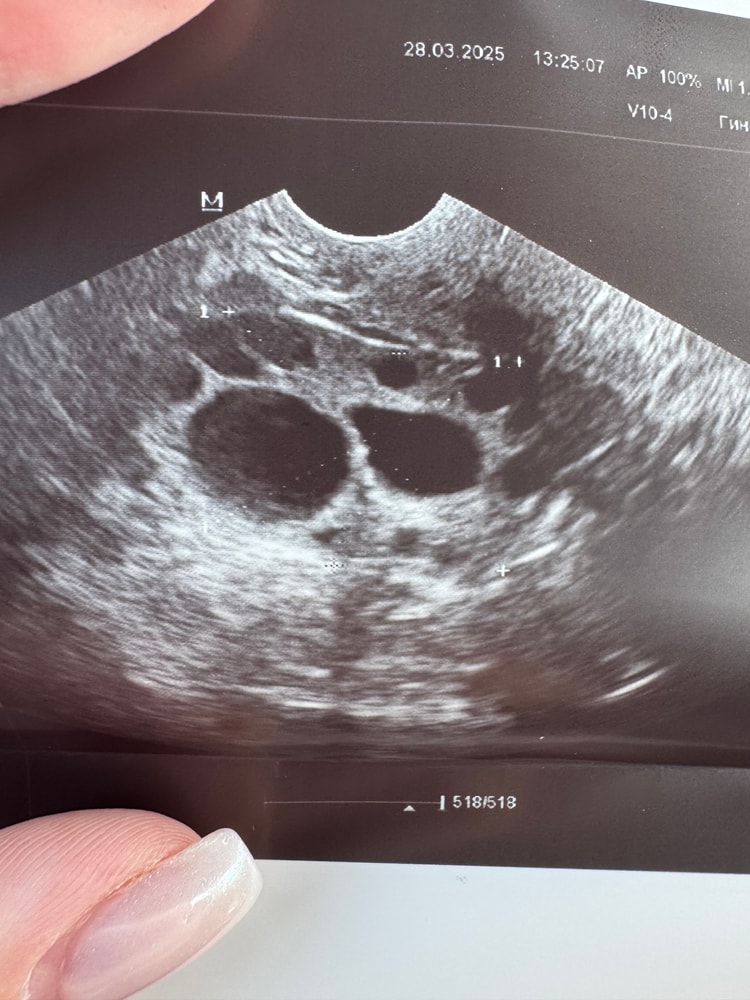

28.03.2025

Дарина , вот я и не знаю когда ставить. Сегодня фолликул 18,6, я думаю, что рано 🥲 завтра будет 19,8 - наверное, оптимально завтра..

Алена, ну слушай, я бы тоже поставила завтра. Будет около 20 точно уже Овуляция была на следующий день, 24 числа. Ощутимая очень

Горохова Диана, моя врач в отпуск ушла, к сожалению( а связи с ней напрямую нет. В прошлый раз мы ставили с ней укол овитрель на размере 19 мм. Но это было на стимуляции. Сейчас мне кажется, что еще маловат, а вот если завтра поставить вечером, он уже будет 19,8 + один день точно дозревать будет после укола.. около 21 мм будет.. Лишь бы яйцеклетка была хорошая, но тут уже не угадаешь 🫣 Просто боюсь ждать 2 дня, чтобы в кисту не перерос. Спасибо ❤️